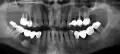

Коронки шатаются, скоро упадут, похоже, вместе с остатками зубов. Подлежат ли восстановлению два зуба под металлокерамическими коронками справа сверху, или только удаление?

Комментарий №175653

• Вы правы, зубы, по данному снимку, подлежат удалению, так как есть воспалительный процесс, резорбция костной ткани, нет твердых тканей коронковой части зуба для последующего восстановления. После удаления, дефект лучше заместить имплантатами. Проконсультируйтесь очно со стоматологом-хирургом.